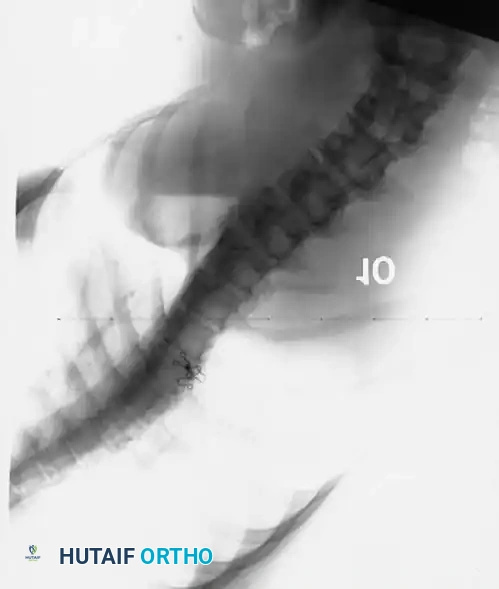

CONCAVE RIB OSTEOTOMIES: HISTORICAL CONTEXT AND BIOMECHANICS

The concept of concave rib osteotomies as a structural release procedure for severe spinal deformity was first introduced by Flinchum in 1963. Subsequently, prominent deformity surgeons including Kostuik, Tolo, Goldstein, and Mann et al. expanded upon its utility, demonstrating its value in mobilizing rigid thoracic and thoracolumbar curves.

The biomechanical rationale for this procedure is rooted in the tension-band effect of the thoracic cage. In severe scoliosis, the ribs on the concave side of the curve become structurally contracted, acting as a rigid tether that resists coronal correction and derotation. Halsall et al. conducted pivotal cadaveric studies testing spinal flexibility before and after the sectioning of ribs on the tension (concave) side. Their findings demonstrated an average increase in coronal deflection of 53%, with the maximum increase in flexibility achieved when five or six apical ribs were resected or osteotomized.